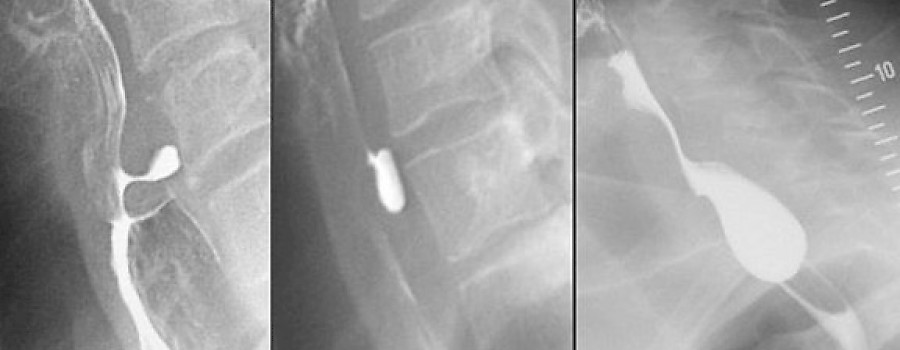

Beim Zenker-Divertikel handelt es sich um ein Divertikel des Hypopharynx (Schlund) und nicht der Speiseröhre, wie häufig falsch angegeben wird.